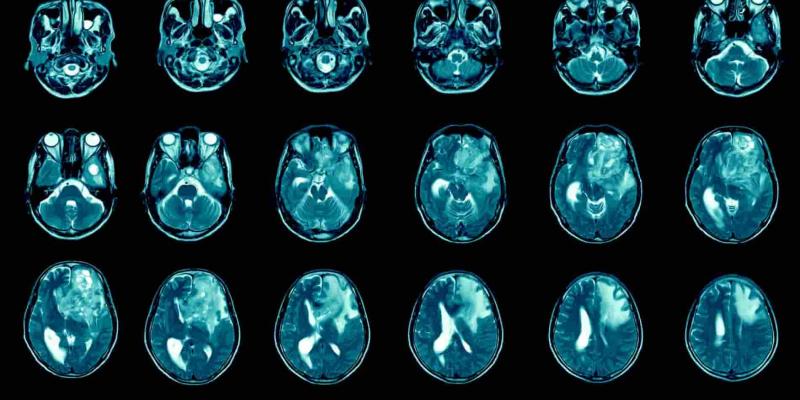

Un grupo de investigadores pertenecientes al Grupo de Cabeza y Cuello y la Unidad de Terapia Molecular del Cáncer (UITM)-CaixaResearch, adscritos al Vall d'Hebron Instituto de Oncología (VHIO), han llevado a cabo un estudio para evaluar la seguridad de un nuevo fármaco epigenético destinado al tratamiento de tumores sólidos avanzados.

La relevancia de esta investigación radica en que se trata del primer ensayo en humanos de un fármaco epigenético de segunda generación dirigido a pacientes con tumores sólidos que habían recibido tratamientos previos o que no eran candidatos para las opciones terapéuticas estándar. Los resultados preliminares de este ensayo han sido publicados recientemente en la revista 'Clinical Cancer Research'.